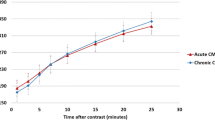

Baseline characteristics are summarised in Table 1. Twenty patients were studied (1.5T n = 10, 3.0T n = 10). CMR was undertaken 3.7 ± 1.3 days post STEMI in the 1.5T group and 3.4 ± 2.1 days post STEMI in the 3.0T group. In total, 171 slices were analysed for IS and AAR (89 at 1.5T, at 82 at 3.0T). All LGE and STIR slices were of diagnostic image quality. Data for IS and AAR are shown in Tables 2, 3 and 4, and Figures 3 and 4.

IS varied significantly with the quantification method (Tables 2 and 3 and Figures 3 and 5). FWHM, 7SD and 8SD closely agreed with manual IS quantification at 1.5T, and 6SD showed weak agreement. FWHM and 8SD closely agreed with manual quantification at 3.0T. At both field strengths, IS was significantly greater with OAT and 5SD compared with manual quantification. IS was also greater with 6SD and 7SD at 3.0T. Bland-Altman plots for agreement with manual quantification are shown in Additional file 2. There was a strong trend towards reduced IS quantification time using FWHM compared with all SD-based methods at both field strengths. The reduction in quantification time with FWHM was highly significant when compared with manual quantification at both field strengths, and when compared with 5SD and 8SD at 1.5T. There was no difference in quantification time using FWHM and OAT (Table 5).

Correlation of myocardial injury with LV ejection fraction

AAR extent

AAR varied with the quantification method used (Figures 4 and 5). There was no significant difference between 2SD, OAT and manually quantified AAR at 1.5T. At 3.0T, AAR quantified with OAT was larger than that manually contoured (p = 0.004) and similar to that on 2SD. Agreement with manual quantification at 1.5T tended to be higher for OAT than 2SD, with ICC 0.920 and narrower limits of agreement on Bland-Altman analysis. There was no difference in AAR quantification time using OAT, 2SD or manual quantification at 1.5T or 3.0T (Table 5), Additional files 4 and 5.